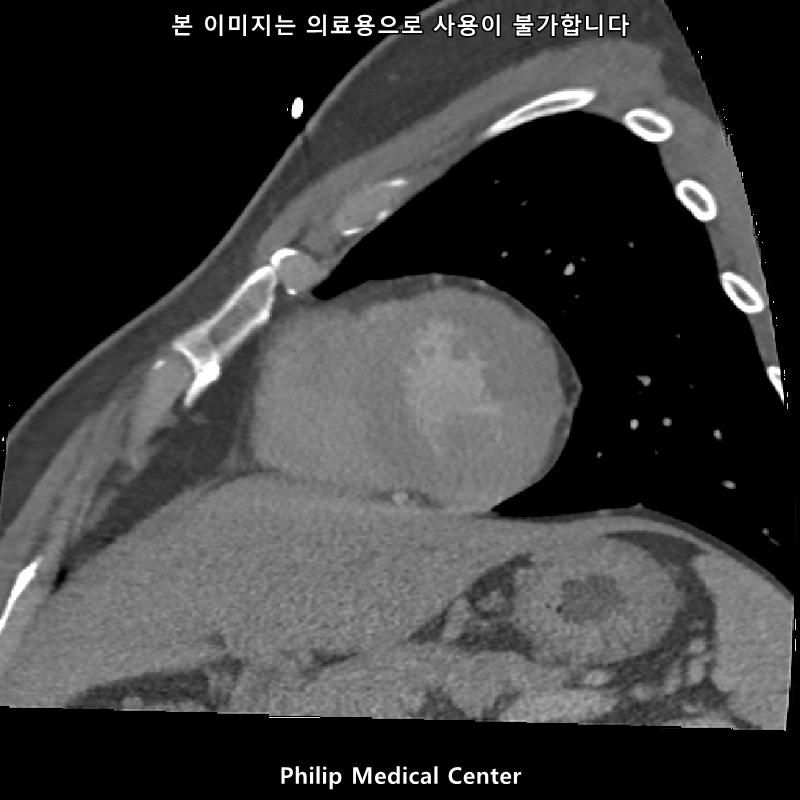

• 1번 째 사진

• 올리신 사진들을 통해서는 폐를 평가할 수 없습니다.

우측 폐첨부에 경미한 섬유성변화와 우중엽에 약 3mm크기의 결절이라는 것은 이상 소견이긴 하지만 보통 경과관찰을 하는 소견입니다.